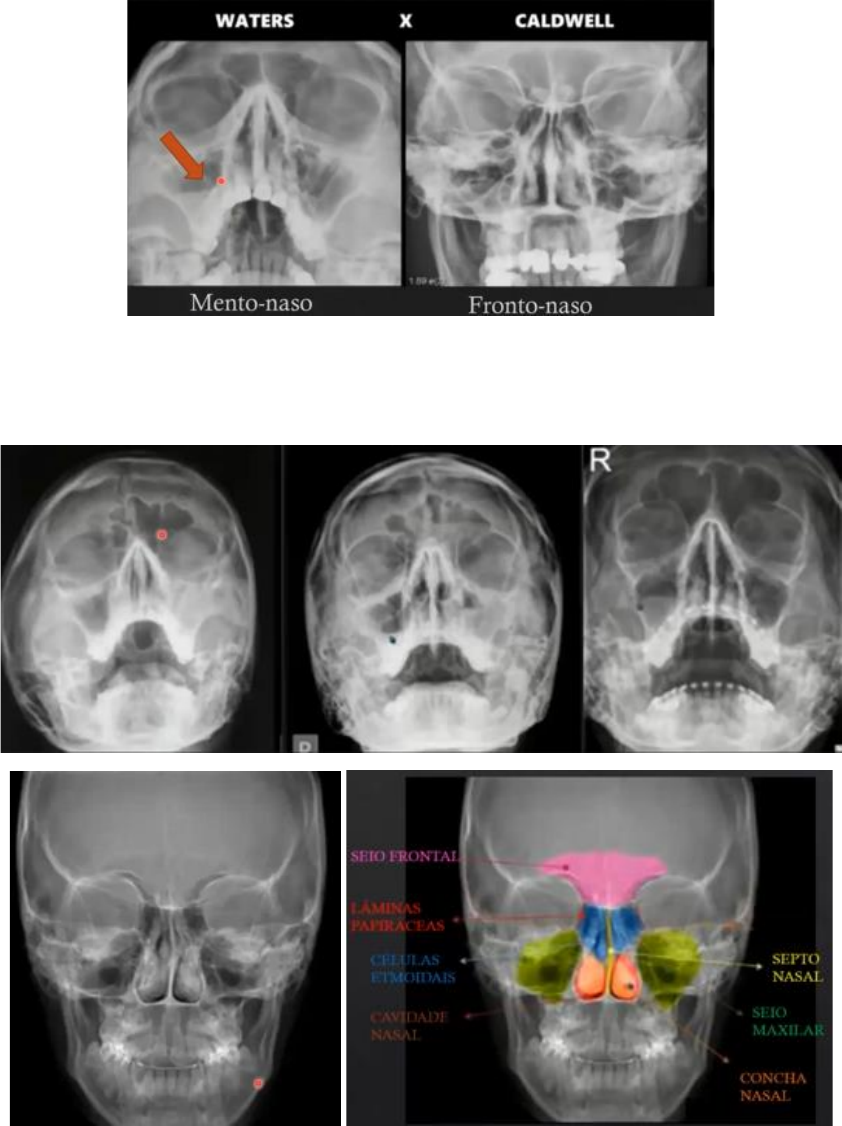

▪ Incidências: mento-naso (queixo para frente) e fronto-naso (fronte para frente)

o Há nível líquido dentro do seio maxilar direito (incidência mento-naso)

▪ A: obliteração do seio maxilar esquerdo (sinusopatia aguda), o seio frontal é assimétrico; B:

obliteração do seio maxilar esquerdo e nível líquido no seio maxilar direito; C: nível líquido no seio

maxilar direito (sinusopatia crônica)